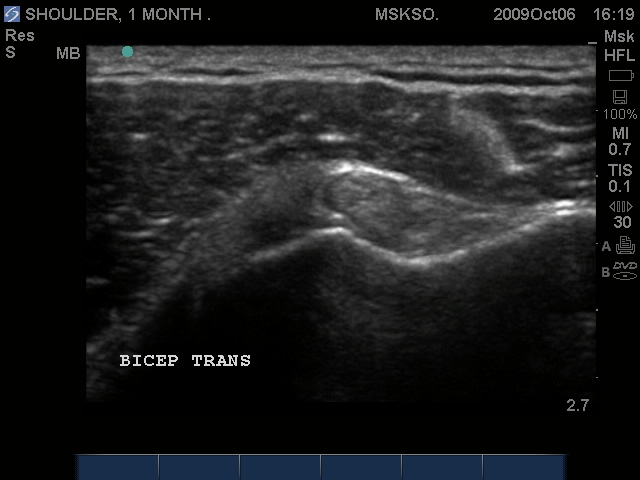

Subluxing Bicep tendon over lesser tuberosity

Subluxing Bicep tendon over proximal lesser tuberosity

Splitting Bicep tendon over lesser tuberosity

Long axis Bicep tendon with synovial fluid at level of surgical neck